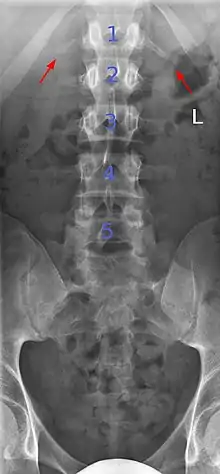

Sacralization of the L5 vertebra is seen at the lower right of the image.

Sacralization of the fifth lumbar vertebra (or sacralization) is a congenital anomaly, in which the transverse process of the last lumbar vertebra (L5) fuses to the sacrum on one side or both, or to ilium, or both. These anomalies are observed in about 3.5 percent of people, and it is usually bilateral but can be unilateral or incomplete (ipsilateral or contralateral rudimentary facets) as well. Although sacralization may be a cause of low back pain, it is asymptomatic in many cases (especially bilateral type). Low back pain in these cases most likely occurs due to biomechanics. In sacralization, the L5-S1 intervertebral disc may be thin and narrow. This abnormality is found by X-ray.

Sacralization of L6 means L6 attaches to S1 via a rudimentary joint. This L6-S1 joint creates additional motion, increasing the potential for motion-related stress and lower back pain/conditions. This condition can usually be treated without surgery, injecting steroid medication at the pseudoarticulation instead. Additionally, if L6 fuses to another vertebra this is increasingly likely to cause lower back pain. [3] The presence of a sixth vertebra in the space where five vertebrae normally reside also decreases the flexibility of the spine and increases the likelihood of injury. [4]